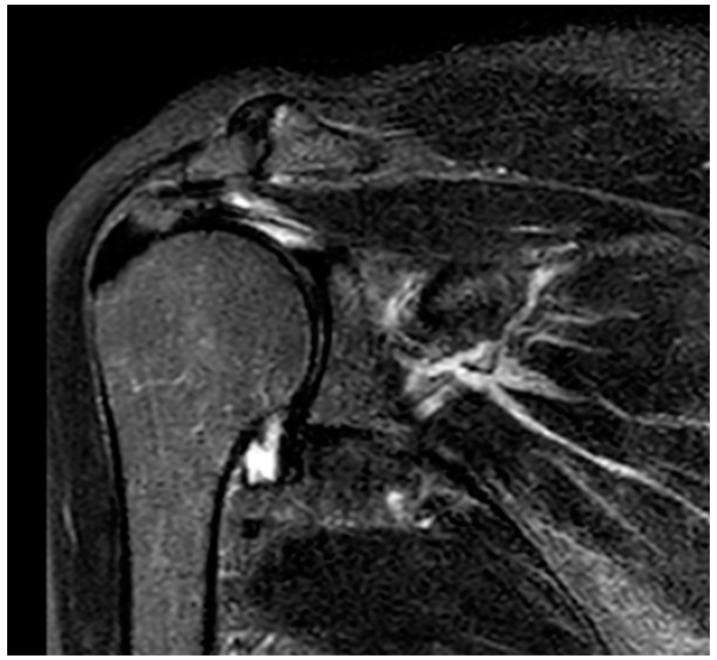

Chronic shoulder pain may cause significant functional disability and reduced psychosocial well-being. Detailed Case Description: In this case, we propose the use of pain neuroscience education and whole-body cryostimulation (WBC) to treat a 64-year-old woman with severe functional limitations and chronic right shoulder pain. The aim was to overcome kinesiophobia and improve her motor function, autonomy, and quality of life. Functional and clinical assessments were conducted at admission, discharge, and at a one-month follow-up via phone call. The patient's global health, shoulder function, and quality of life showed improvement during hospitalisation and were maintained after one month.

慢性肩部疼痛可能导致严重的功能障碍和心理社会幸福感下降。详细病例描述:在本病例中,我们建议使用疼痛神经科学教育和全身冷冻刺激(WBC)来治疗一名64岁的女性,她存在严重的功能受限和慢性右肩疼痛。目的是克服运动恐惧,改善她的运动功能、自主性和生活质量。在入院时、出院时以及通过电话进行的一个月随访时进行了功能和临床评估。患者的整体健康状况、肩部功能和生活质量在住院期间有所改善,并在一个月后得以维持。